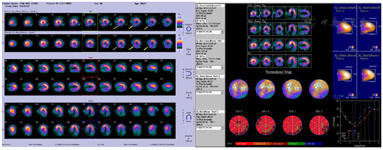

两日法99Tcm-MIBI运动负荷+静息心肌血流灌注显像,基础心率82次/min,基础血压126/81 mmHg(1 mmHg=0.133 kPa);负荷后高峰心率142次/min,负荷高峰血压197/102 mmHg,运动量达次级量,负荷ECG未见明显ST段下降。心肌灌注显像提示部分后间隔中段及基底段、部分下壁中段及基底段(RCA供血区)心肌缺血,约占左心室面积12%;部分下壁基底段(RCA供血区)、部分后侧壁中段、后侧壁基底段(LCX供血区)心肌梗死,约占左心室面积12%。左心室整体收缩功能正常(图1)。

行两日法99Tcm-MIBI运动负荷+静息心肌灌注显像,提示部分后间隔中段及基底段、部分下壁中段及基底段(RCA供血区)心肌缺血,约占左心室心肌面积12%;部分下壁基底段(RCA供血区)、部分后侧壁中段及基底段(LCX供血区)心肌梗死,约占左心室心肌面积12%。左心室整体收缩功能正常。